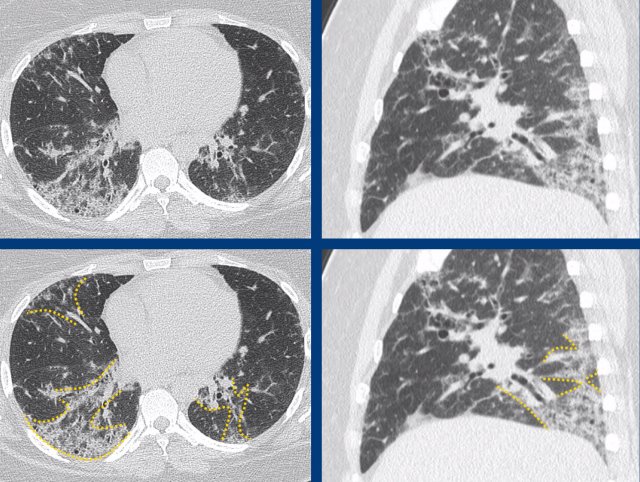

The images show a combination of basal dominant groundglass and traction bronchiectasis, combined with limited perilobular arcade-like consolidations due to co-existing organizing pneumonia (OP).

The final diagnosis was fibrotic NSIP in anti-synthetase syndrome.

Anti-synthetase syndrome is an immune-mediated multisystem disorder that can include (among others) interstitial lung disease, myositis and/or polyarthritis, skin changes and Raynaud’s phenomenon.